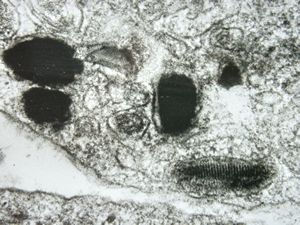

M,15y. | megamitochondria with lamellar inclusions in hepatocyte - Wilson disease